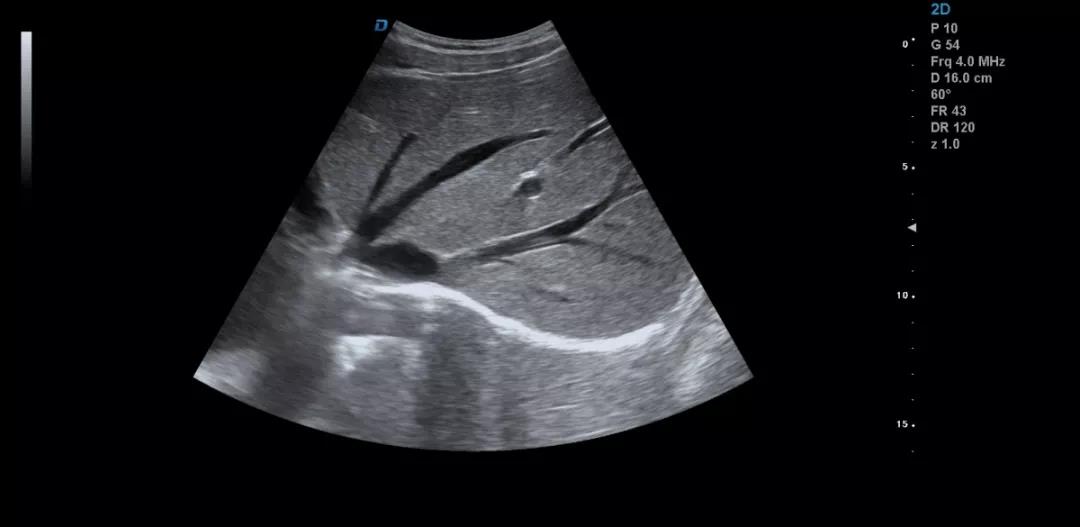

眾所周知,肝臟有很多檢查死角,成為超聲檢查的盲區(qū),如肺和骨所掩蓋處,肝右前上段及右后上段的膈頂部,左外葉外側(cè)角區(qū),沿肝臟表面的肋骨下區(qū)等等部位,只有極其細(xì)致的檢查配上精巧的手法才能盡可能的顯示清楚這些部位。

如果我們能夠細(xì)致的檢查每個(gè)病人,所謂的肝臟死角能夠盡可能的探測到,肝臟的死角其實(shí)只有膈頂部,其他的部位如果能細(xì)致檢查都可以探測到。

發(fā)現(xiàn)肝臟病變時(shí)要多切面多角度掃查,可以了解病變的解剖位置并排除假陽性。